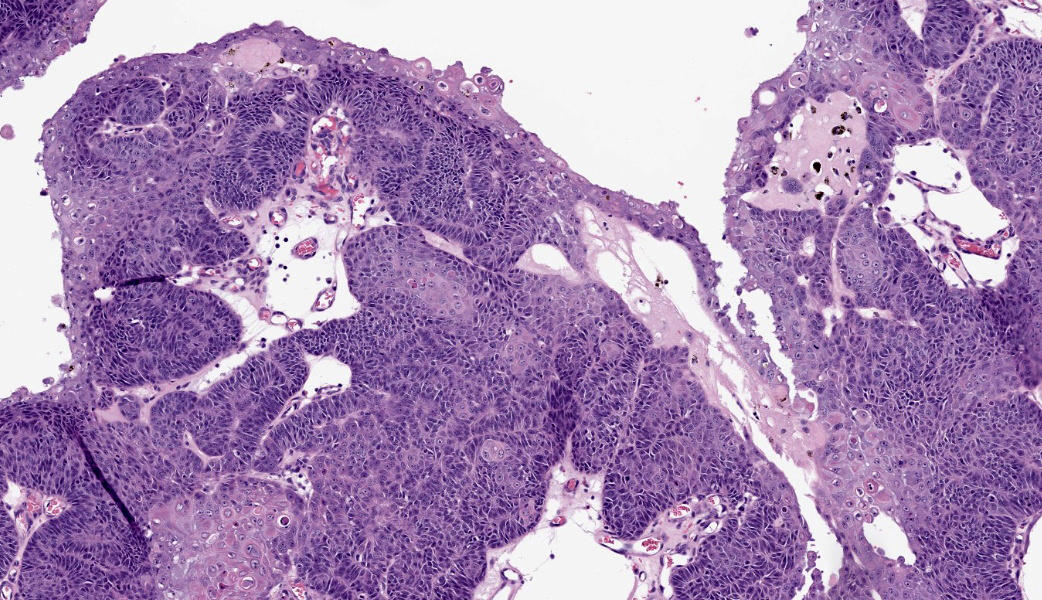

Haired skin: Extending from the dermis deep into the subcutis is an approximately 2 x 2 cm well-demarcated cystic mass lined by neoplastic undifferentiated basaloid epithelial cells. The neoplastic cells are arranged in lobules of dense anastomosing and palisading cords or small tightly packed nests, supported by scant fibrovascular stroma. There are multifocal papillary projections of neoplastic lobules into the lumen of the large cystic cavity. Multifocai lobules have smaller central cyst formation. The neoplastic basaloid cells are cuboidal with scant basophilic cytoplasm and round to oval, hyperchromatic nuclei, with two or more prominent nucleoli. There is minimal anisocytosis and moderate anisokaryosis. There is multifocal abrupt squamous differentiation and necrosis and approximately 5 mitotic figures per high power field. Brown granular pigment, most consistent with melanin, is present throughout the periphery of the mass; multifocal melanomacrophages infiltrate neoplastic lobules. Neoplastic cells extend to within 2 mm of the surgical margin; however, there are multifocal foci suspicious for local invasion.Contributor's Morphologic Diagnoses:

Histologically, basosquamous carcinomas are predominately composed of intradermal to subcutaneous lobules of undifferentiated basal cells with central foci of abrupt squamous differentiation.1 Keratinocytes at the center of neoplastic lobules have mild “nuclear pleomorphism, mitotic activity and dyskeratosis.”1 Unlike other epidermal neoplasms, connection to the overlying epidermis is not a consistent diagnostic feature.4 However, cyst formation and melanization, as seen in this case, are common and can often be appreciated grossly.1,4 Keratinocytes, present in the foci of abrupt and atypical keratinization, that display features of malignancy, along with “the lack differentiation of the follicular isthmus or bulb are features that help differentiate basosquamous carcinomas” from other tumors.4

In human literature, it is currently believed that the BSC initially arises as a BCC that then undergoes genetic and epigenetic alterations, ultimately leading to squamous differentiation through basal-to-squamous transition (BST). As such, the BSC was classified as a BCC variant by the WHO in 2023.7 To further complicate matters, there are also “basaloid SCC” and “keratotic BCC” diagnoses in humans, as well as BCC/SCC collision tumors.7 Participants were shown histologic images of what the moderator currently uses to differentiate between a keratinizing BCC, a basaloid SCC, and a BSC. The basaloid SCC is typically described as having comedonecrosis with squamous differentiation at the edges of lobules and is NOT classified as a skin tumor. Rather, it is found in the oral cavity, cervix, lung, etc.7 The keratotic BCC variant is composed of horn cysts, parakeratotic cells, and abrupt keratinization.7 BSC is identified by abrupt squamous differentiation (not abrupt keratinization) with dyskeratotic squamous cells within the center of lobules of basal cells.7 Both the basal cells and keratinocytes have mitotic activity. Considering these factors, a diagnosis of BSC was favored by participants. Ultimately, though, there seems to be substantial disagreement on how to define the BSC in veterinary literature, even between prominent tumor texts and fascicles.